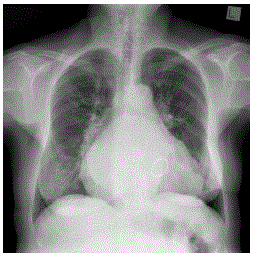

João Pedro, de 5 meses, apresenta tosse, coriza e febre baixa há 3 dias. Hoje ele foi trazido ao plantão por apresentar cansaço, seu primeiro episódio. Você prontamente faz o diagnóstico de bronquiolite viral aguda e segue essa conduta: